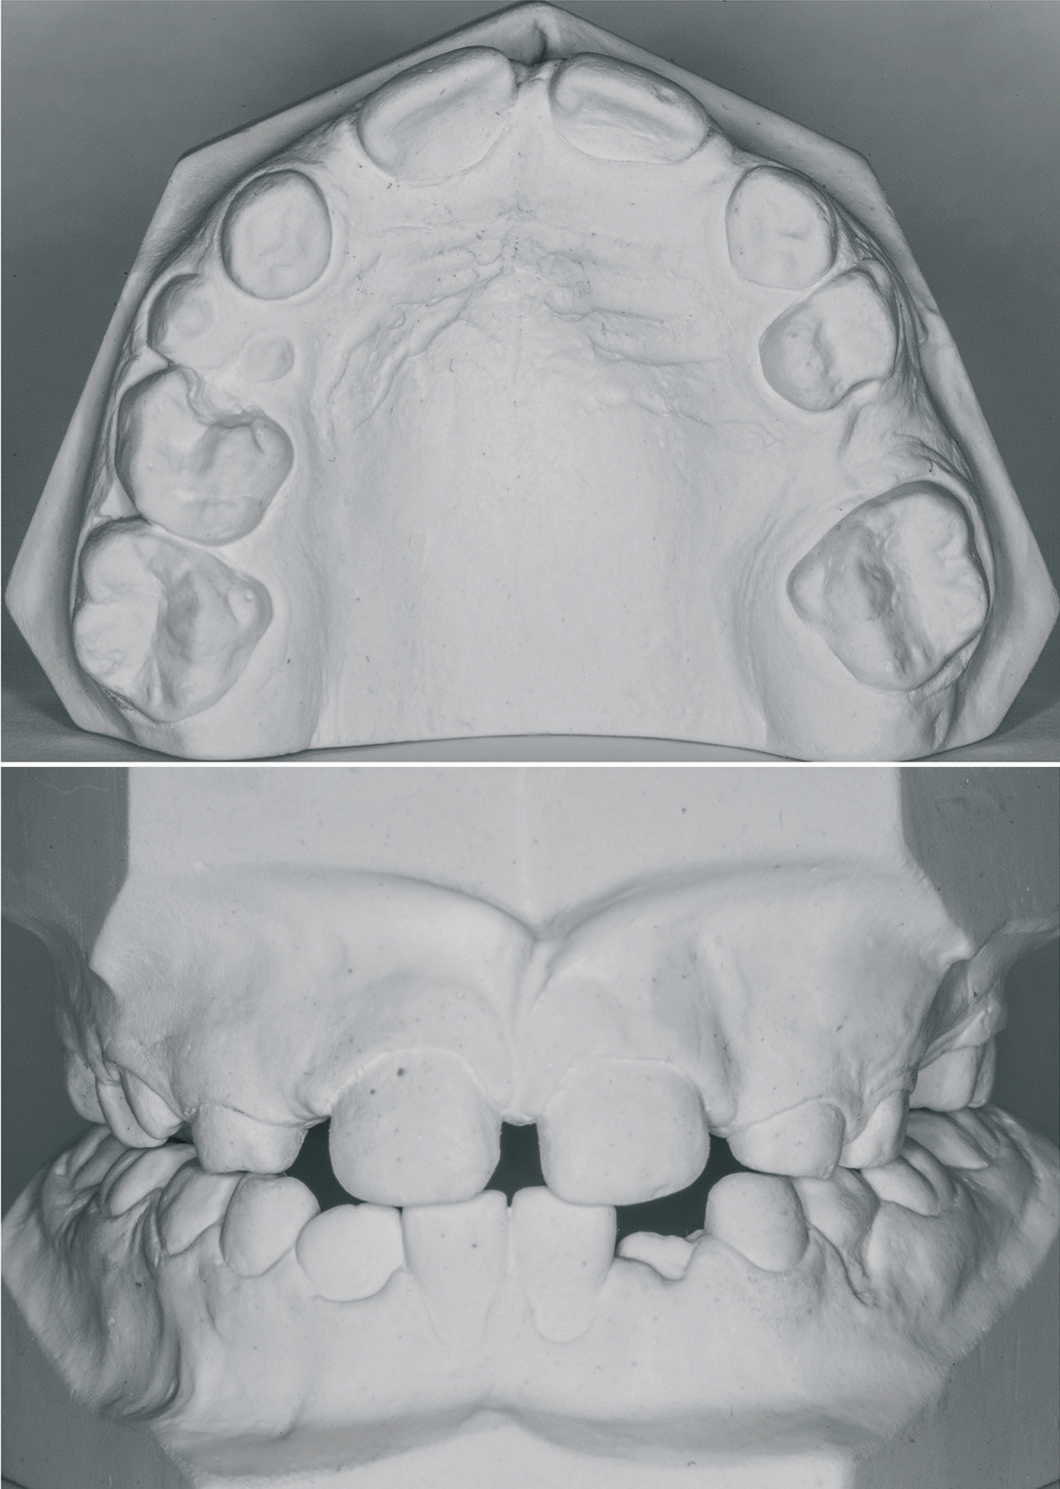

Aufgabenstellung

Zu diesem Prüfungsabschnitt gehörte es, eine dreidimensionale KFO-Befunderhebung durchzuführen, strikt nach Formular (Abb. 4). In das Schema mussten sämtliche Ist-/Soll-Werte, Fehlstellungen und Anomalien eingetragen werden. Am Ende stand der Vorschlag einer Therapieplanung und diese sollte natürlich der Aufgabenstellung der Prüfung entsprechen (Abb. 5). Zum Ermitteln der Werte benötigten die Prüfungsteilnehmer das „Korkhaus“-Besteck – hiermit wurden sämtliche Istwerte aufgenommen und die Sollwerte errechnet (Abb. 6).

- Die Situation wies eine retrudierte Front und ein Diastema mediale auf. Zum Schließen des Diastemas wurde vestibulär eine Fingerfeder am Labialbogen angelötet. Als Lot wurde ein niedrig schmelzendes Universal-Silberlot (Henry Schein) herangezogen. Dieses eignet sich sehr gut zum Löten mit der Handflamme und somit musste nicht das Wasserstofflötgerät benutzt werden. Da die Frontzähne protrudiert werden sollten, wurde ein palatinales Federelement verwendet. Zum Aktivieren der Protrusionsfeder wurden zwei Loops gebogen, ein Vorgang, der dann mit der Retention in der Basisplatte endete.

- Eine transversale Kompression im Seitenzahnbereich war ebenfalls vorhanden, diese sollte mit einer Dehnschraube (Dentaurum) gedehnt werden. In solch einem Fall wird dem Patienten vom Behandler regulär ein Schlüssel zur selbstständigen Aktivierung mitgegeben.

- Der Durchbruch des Zahnes 25 war durch die Aufwanderung des Zahnes 26 verhindert; dieser sollte mit einer Sektorenschraube (Dentaurum) wieder distalisiert werden. Da hierfür der Platz sehr gering war, konnte nur die Mini-Variante der Sektorenschraube gewählt werden.